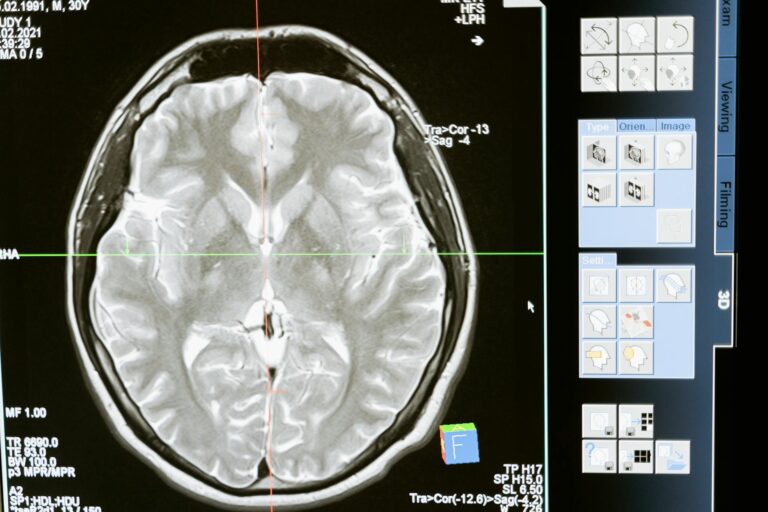

The DMN is a network of brain regions that are active when an individual is at rest or not engaged in any specific task. It was first discovered in 2001 by Marcus Raichle, a neuroscientist at Washington University in St. Louis. The DMN includes various brain regions such as the medial prefrontal cortex, posterior cingulate cortex, and the inferior parietal cortex. These regions are connected by neural pathways and work together to regulate our mental processes during restful states.

In Alzheimer’s disease, the DMN becomes disrupted, leading to dysfunction and impairments in cognitive functioning. Studies have shown that individuals with Alzheimer’s have reduced DMN activity, especially in the posterior cingulate cortex and medial prefrontal cortex. This dysfunction can manifest as memory loss, language difficulties, and changes in behavior and personality.

One of the earliest signs of Alzheimer’s is the accumulation of amyloid plaques and tau tangles in the brain. These protein deposits disrupt the communication between brain cells, causing damage and ultimately leading to cell death. Studies have found that these protein deposits directly affect the DMN regions, leading to its dysfunction.

Moreover, as the disease progresses, the brain’s overall connectivity reduces, causing further impairment of the DMN. This reduction in connectivity is associated with a decline in cognitive functioning and an increase in symptoms of Alzheimer’s.